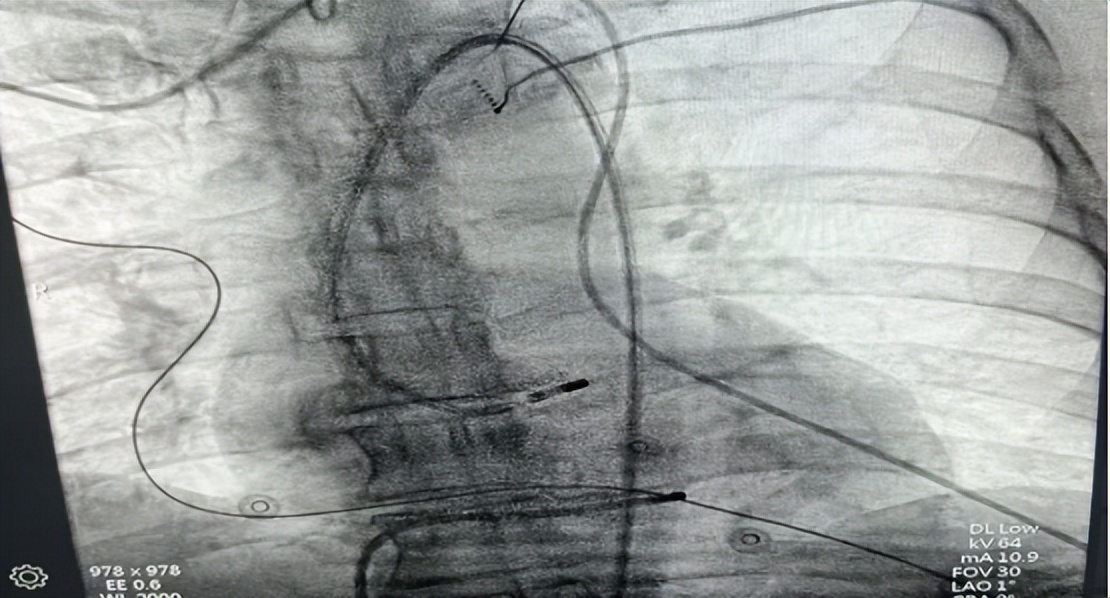

△术中导管放置

△导管图